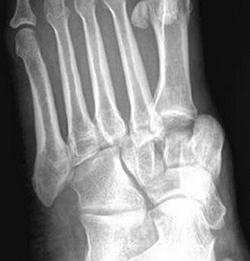

(Слева) При рентгенографии стопы в передне-задней проекции определяется смещение таранной кости кпереди и медиально. Ладьевидная и пяточная кости вместе с остальными костями стопы смещены латерально.

(Справа) У этого же пациента при рентгенографии голеностопного сустава, выполненной в проекции суставной щели, визуализируется латеральное смещение задней суставной поверхности пяточной кости и суставной поверхности ладьевидной кости. Латеральный вывих подтаранного сустава встречается реже, чем медиальный. (Слева) У этого же пациента при КТ в сагиттальной плоскости в коаном режиме, выполненной после неудачной попытки репозиции, определяется импрессионный перелом таранной кости, который возник вследствие ее сдавливания задней суаавной поверхноаью пяточной кости. Этот перелом послужил препятствием для выполнения репозиции.